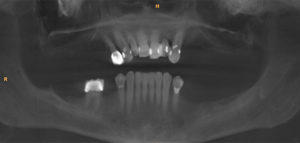

All on 4 Case 1

Before

After after all on 4 x-ray view female patient case 1